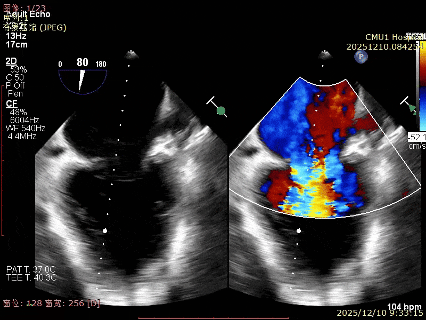

患者食道胃底静脉曲张,遂行TTE术前评估

术前TTE评估:

MR反流病因:DMR(部分腱索断裂)、Carpentier II型;

反流程度:极重度(5+),PISA法估测EROA约1.12cm²,R-VOL约98ml;

病变情况:P2-部分P3,脱垂宽度约27mm ,连枷间距11-13mm,瓣口面积7.8cm²,PML约25mm

其他:TR(重度) ,间接估测PASP约65mmHg;

预估手术难点:后叶冗长,脱垂宽度大,连枷间距大。

为了避免长时间TEE对食道造成损伤,术前即刻3D-TEE短时进一步明确二尖瓣病变相关解剖情况。